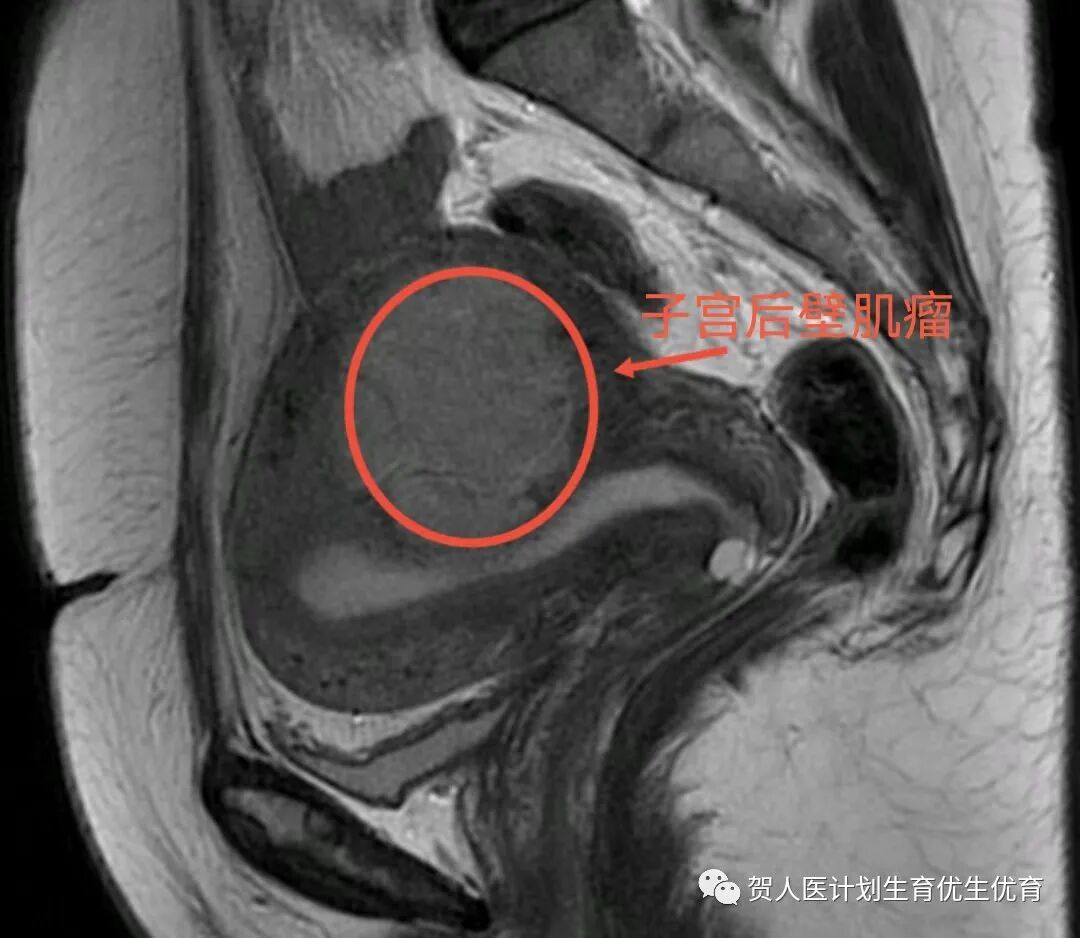

患者术前磁共振检查

案例一:患者刘某青,2021年7月因“发现子宫肌瘤3年,月经增多4个月”来我院就诊。妇科检查发现子宫增大如妊娠2月大小,B超提示子宫占位,子宫肌壁探及79*66mm低回声团,肿瘤压迫子宫内膜,考虑子宫肌瘤。诊断子宫肌瘤。入院后排除禁忌后行子宫肌瘤微波消融术,术后顺利出院,无不良反应。今年7月回访患者,无不适症状,月经量正常,B超提示子宫肌壁低回声团54*51mm,体积较前缩小达62%。